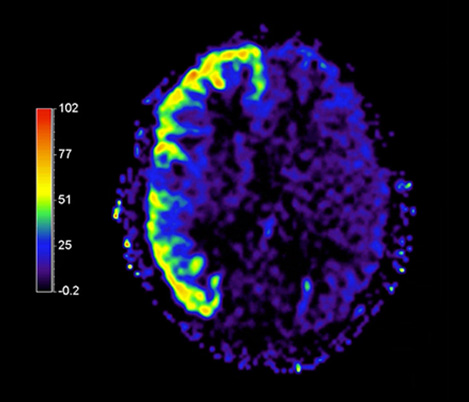

70% of radiologists consider neuro indications to be challenging, mostly due to a lack of appropriate imaging and visualization techniques¹. Philips aims to provide the best possible diagnostic clarity and treatment guidance for all patients with neurological disorders.

By leveraging our dStream digital platform, this year, we are introducing, a set of novel imaging and visualization strategies. These may empower you to resolve complex neuro questions with more certainty, as well as unlock new neuro territories in advanced Neurofunctional applications. This is a key step towards elevating neuro diagnostics and ultimately touching more lives with MR imaging.

New neuro applications

Take a look at our other neuro applications